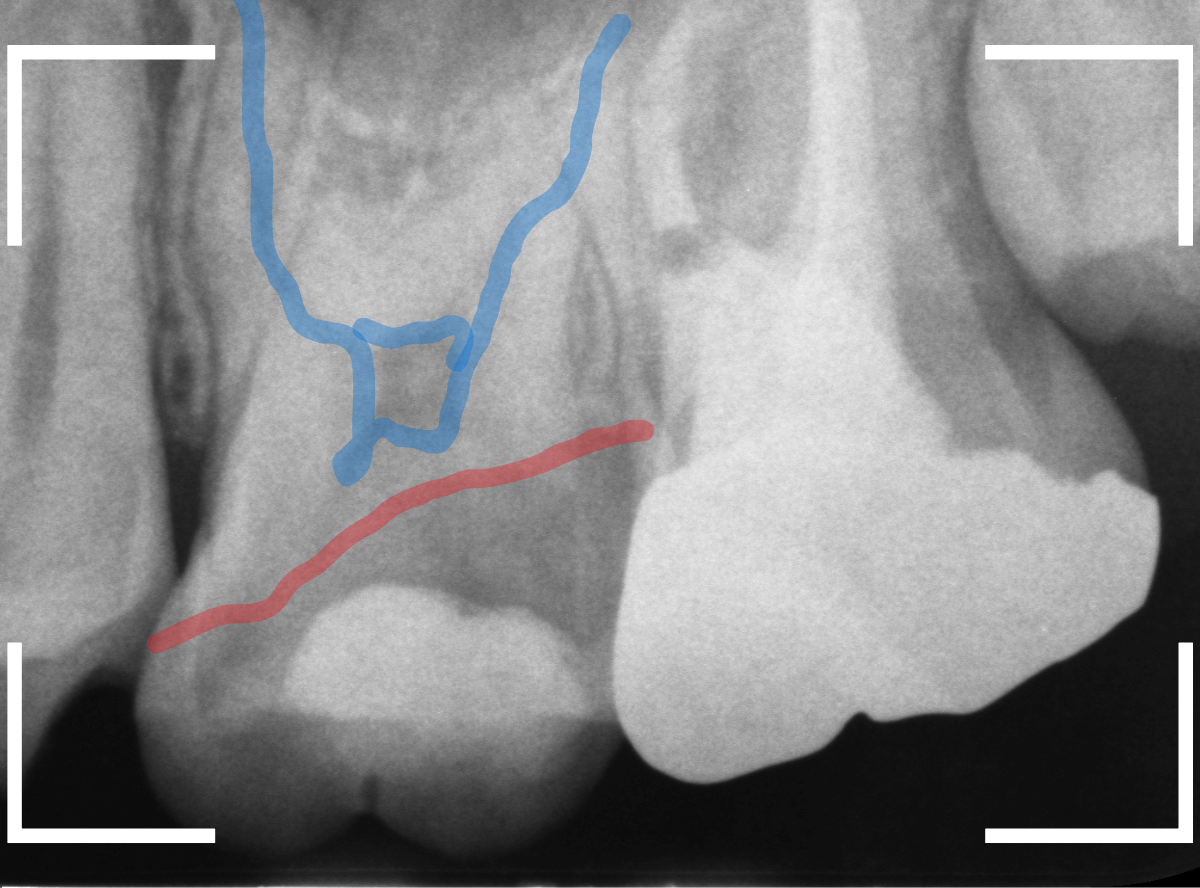

レントゲン写真で確認します。

青い線が歯の神経です。

赤い線が虫歯と思われる部分です。

思った通り、神経に達してしまいそうな大きな虫歯です。

患者さんには、神経を取る治療が必要な可能性が高い事を説明します。